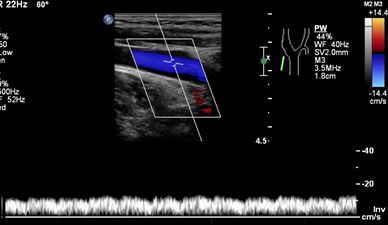

看一看正常的颈内静脉搏动性频谱形态:

正常颈内静脉频谱受心脏搏动影响具有搏动性。但是当上腔静脉阻塞时,双侧颈内静脉、锁骨下静脉及头臂静脉回流障碍,流速会减慢;心脏的搏动不能影响到上述血管,因此上述血管的频谱形态变得平直,呈低速带状血流频谱。患者会出现面颈部及上肢的肿胀,上腹部会出现曲张的浅静脉,而且浅静脉血流的方向是向下的。